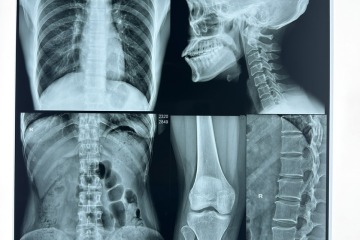

طبی تشخیص کی تیز رفتار دنیا میں، قابل اعتماد امیجنگ حل کی مانگ کبھی زیادہ نہیں رہی۔ دنیا بھر میں صحت کی دیکھ بھال فراہم کرنے والے اور لیبارٹریز درست نتائج فراہم کرنے کے لیے اعلیٰ کارکردگی والے ٹولز پر انحصار کرتے ہیں، اور HYC میڈیکل تھرمل فلم اس میدان میں ایک گیم چینجر کے طور پر نمایاں ہے۔ کلینیکل سیٹنگز کی سخت ضروریات کو پورا کرنے کے لیے ڈیزائن کیا گیا، HYC میڈیکل تھرمل فلم جدید تھرمل امیجنگ ٹیکنالوجی کو مربوط کرتی ہے تاکہ یہ یقینی بنایا جا سکے کہ ہر اسکین واضح، تفصیلی تصاویر کیپچر کرتا ہے — بیماری کی درست شناخت اور علاج کی منصوبہ بندی کے لیے اہم عام امیجنگ مواد کے برعکس، HYC میڈیکل تھرمل فلم خام مال کے آئن سے لے کر حتمی پیداوار تک سخت کوالٹی کنٹرول کے عمل سے گزرتی ہے، اس بات کو یقینی بناتی ہے کہ HYC میڈیکل تھرمل فلم کا ہر رول لیبارٹری کے درجے کے معیارات پر پورا اترتا ہے جو مجموعی تشخیصی معیارات کو بلند کرتا ہے۔

HYC، جدید میڈیکل امیجنگ سلوشنز کا علمبردار، HYC کی بغیر کسی رکاوٹ کے یونیفائیڈ میڈیکل ہیٹ سینسیٹیو فلم برائے پرنٹنگ کی نقاب کشائی کرنے پر بہت پرجوش ہے— ایک گیم بدلنے والی پروڈکٹ جو صحت کی دیکھ بھال میں پیشہ ورانہ صلاحیت کے امیج آؤٹ پٹ کے لیے نئے معیارات قائم کرنے کے لیے تیار کی گئی ہے۔ پرنٹنگ کے لیے HYC کی بغیر کسی رکاوٹ کے یونیفائیڈ میڈیکل ہیٹ سینسیٹیو فلم کرکرا، تفصیلی تصاویر فراہم کرنے کے لیے جدید ترین ہیٹ حساس ٹیکنالوجی کا فائدہ اٹھاتی ہے، جو کہ صحت کی دیکھ بھال کی سہولیات کی فوری ضرورتوں کو براہ راست حل کرتی ہے جو مریض کی درست تشخیص اور علاج کی منصوبہ بندی کے لیے عین امیجنگ پر منحصر ہے۔ HYC کی میڈیکل امیجنگ لائن اپ کے بنیادی حصے کے طور پر، پرنٹنگ کے لیے HYC کی بغیر کسی رکاوٹ کے یونیفائیڈ میڈیکل ہیٹ سینسیٹو فلم زیادہ تر میڈیکل امیجنگ ڈیوائسز کے ساتھ ہم آہنگی میں کام کرتی ہے، جس سے HYC کی بغیر کسی رکاوٹ کے یونیفائیڈ میڈیکل ہیٹ سینسیٹیو فلم پرنٹنگ کے لیے مصروف اسپتالوں اور کلینکوں کے لیے بہترین انتخاب ہے جس کا مقصد ورک فلو کو بڑھانا ہے۔

تشخیصی امیجنگ کی زمین کی تزئین ایک تبدیلی سے گزر رہی ہے، جس میں درستگی اور وشوسنییتا غیر گفت و شنید کے معیار بنتے جا رہے ہیں۔ تشخیصی امیجنگ کے لیے HYC پریمیم تھرموسینسیٹیو میڈیکل فلم اس تبدیلی میں سب سے آگے ہے، طبی امیجنگ فلمیں کیا حاصل کر سکتی ہیں اس کی وضاحت کرنے کے لیے کلینکل گریڈ کی پائیداری کے ساتھ جدید ترین تھرموسینسیٹیو ٹیکنالوجی کو ضم کرتی ہے۔ تشخیصی امیجنگ کے لیے HYC پریمیم تھرموسینسیٹیو میڈیکل فلم محض ایک پروڈکٹ نہیں ہے بلکہ درست طبی فیصلہ سازی کو بااختیار بنانے کے لیے انجنیئر کردہ ایک ٹول ہے، اس بات کو یقینی بناتے ہوئے کہ صحت کی دیکھ بھال فراہم کرنے والوں کے پاس مریضوں کی دیکھ بھال کی رہنمائی کے لیے واضح ترین ممکنہ بصری ڈیٹا موجود ہے۔

صحت کی دیکھ بھال کی تیز رفتار دنیا میں، جب وقت کی حساس تشخیص کی بات آتی ہے تو ہر سیکنڈ کا شمار ہوتا ہے۔ HYC، میڈیکل امیجنگ سلوشنز میں ایک سرکردہ اختراع کرنے والا، HYC کی تیز رفتار پروسیسنگ میڈیکل تھرمل ڈرائی امیج فلم متعارف کروانے پر فخر محسوس کر رہا ہے، جو کہ صحت کی دیکھ بھال فراہم کرنے والے اہم تشخیصی طریقہ کار کو کیسے ہینڈل کرتے ہیں اس کو تبدیل کرنے کے لیے ڈیزائن کیا گیا ہے۔ HYC کی میڈیکل تھرمل ڈرائی امیج فلم روایتی امیجنگ مواد کے لیے مطلوبہ وقت کے ایک حصے میں اعلیٰ معیار کے نتائج فراہم کرنے کے لیے تیار کی گئی ہے، اس بات کو یقینی بناتے ہوئے کہ طبی پیشہ ور افراد باخبر فیصلے جلد اور درست طریقے سے کر سکیں۔

طبی تشخیص کے دائرے میں، درستگی اور رفتار سب سے اہم ہے۔ HYC کی تازہ ترین اختراع، میڈیکل تھرمل ڈرائی امیج فلم، میڈیکل امیجنگ میں کارکردگی کو نئے سرے سے متعین کرنے کے لیے ایک تبدیلی کے آلے کے طور پر ابھرتی ہے۔ میڈیکل تھرمل ڈرائی امیج فلم کو صحت کی دیکھ بھال کی سہولیات کو درپیش دیرینہ چیلنجوں سے نمٹنے کے لیے تیار کیا گیا ہے، جو روایتی اختیارات کے لیے ایک ہموار متبادل پیش کرتی ہے۔ میڈیکل انک جیٹ بلیو فلم سے جڑے بوجھل عمل کے برعکس، میڈیکل تھرمل ڈرائی امیج فلم پرنٹنگ کے لمحے سے آپریشنز کو ہموار کرتی ہے، اس بات کو یقینی بناتی ہے کہ صحت کی دیکھ بھال فراہم کرنے والے لاجسٹک تاخیر کے بجائے مریضوں کی دیکھ بھال پر توجہ دے سکتے ہیں۔

میڈیکل امیجنگ کے انتہائی مسابقتی دائرے میں، HYC کی حسب ضرورت، ہائی ڈیفینیشن تھرمل فلم ایک تبدیلی کی قوت کے طور پر ابھرتی ہے، جس سے صحت کی دیکھ بھال کرنے والے پیشہ ور افراد طبی امیجز کو حاصل کرنے، تجزیہ کرنے اور تشریح کرنے کے طریقے میں انقلاب برپا کرتے ہیں۔ یہ جدید ترین پروڈکٹ نہ صرف بے مثال وضاحت اور درستگی پیش کرتا ہے بلکہ میڈیکل تھرمل ڈرائی امیج فلم اور میڈیکل انک جیٹ بلیو فلم جیسے روایتی آپشنز کے مقابلے میں بھی نمایاں ہے۔